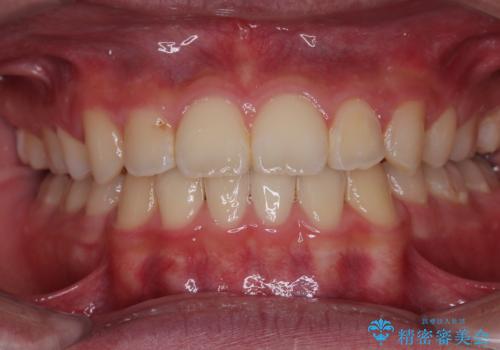

インビザラインは、装着していない時間がどれだけ短いかが、治療期間を大きく左右します。こちらの患者様は1日22時間以上、毎日欠かさず装着してくださったため、1年強という短期間で満足のいく歯列に整えることができました。